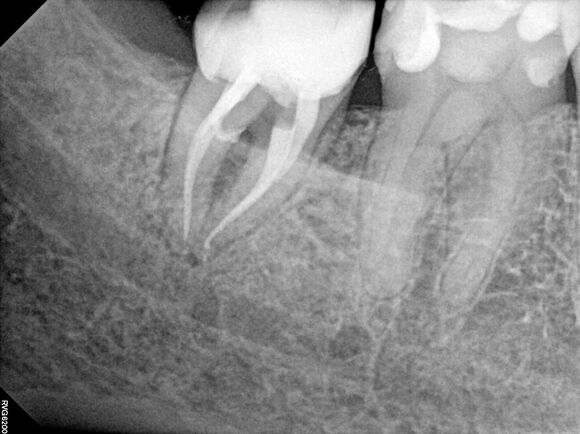

Beispiel 1: Vorher

Schwierige Krümmungen und sehr grazile Wurzeln.

Beispiel 1: Nachher

Die perfekte Wurzelfüllung!